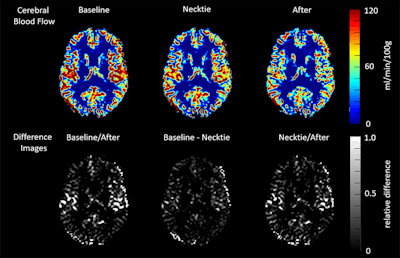

The researchers used an arterial spin labeling (ASL) scanning protocol, with quantitative phase-contrast angiography performed over the jugular vein during a full RR cycle. Cerebral blood flow (CBF) was calculated and venous flow in the jugular vein was measured using software. CBF values were rendered as mL/min/100 g.

In the necktie group, cerebral blood flow dropped by 4.33 mL/min/100 g, or 7.5%, from the baseline scan to the second scan when the necktie was tightened. It was even lower at the third scan, 12.8% from baseline, after the necktie had been loosened. There were no statistically significant changes in CBF in the control group between the different scans.